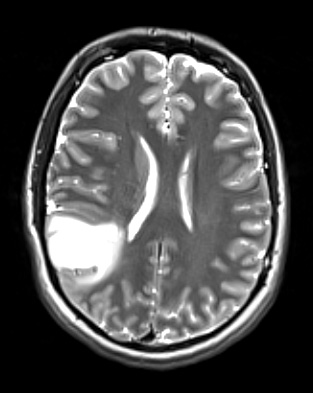

Case 17 History ---- The patient is a 21-year-old man presenting with new onset of seizure-like activity. MRI shows a right parietal lobe cortical based non-enhancing lesion. Operative procedure: IMRI right parietal craniotomy for tumor resection. ---- 17A1 The right parietal tumor is hyperintense in this T2-weighted scan with applied contrast.